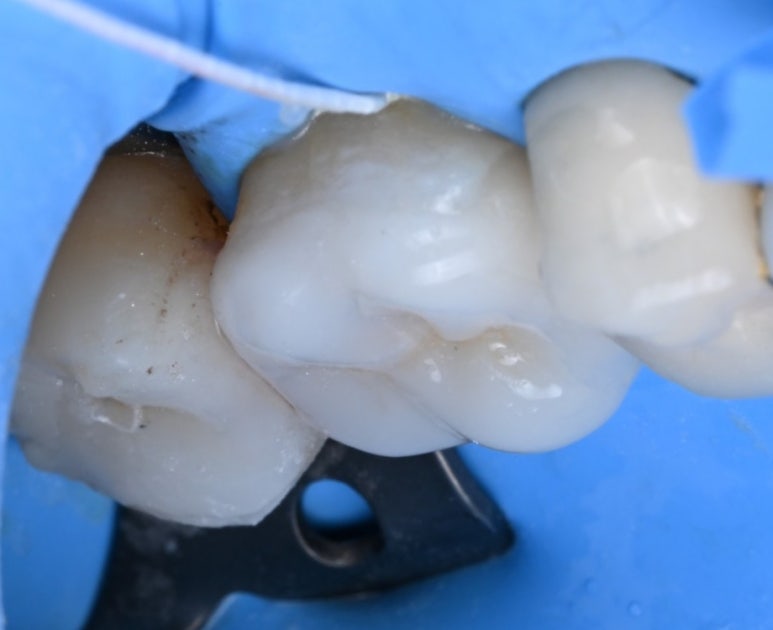

25.11.11 #17 치아의 금 인레이가 탈락하고 충치가 발생한 모습.

문제가 된 큰 어금니를 치료하던 중,

바로 앞쪽 어금니(#16)의 상태도

심상치 않음을 발견했습니다.

이 치아 역시 금 인레이가 되어 있었는데,

틈새로 비쳐 보이는 내부가

이미 충치로 오염되어 있었습니다.